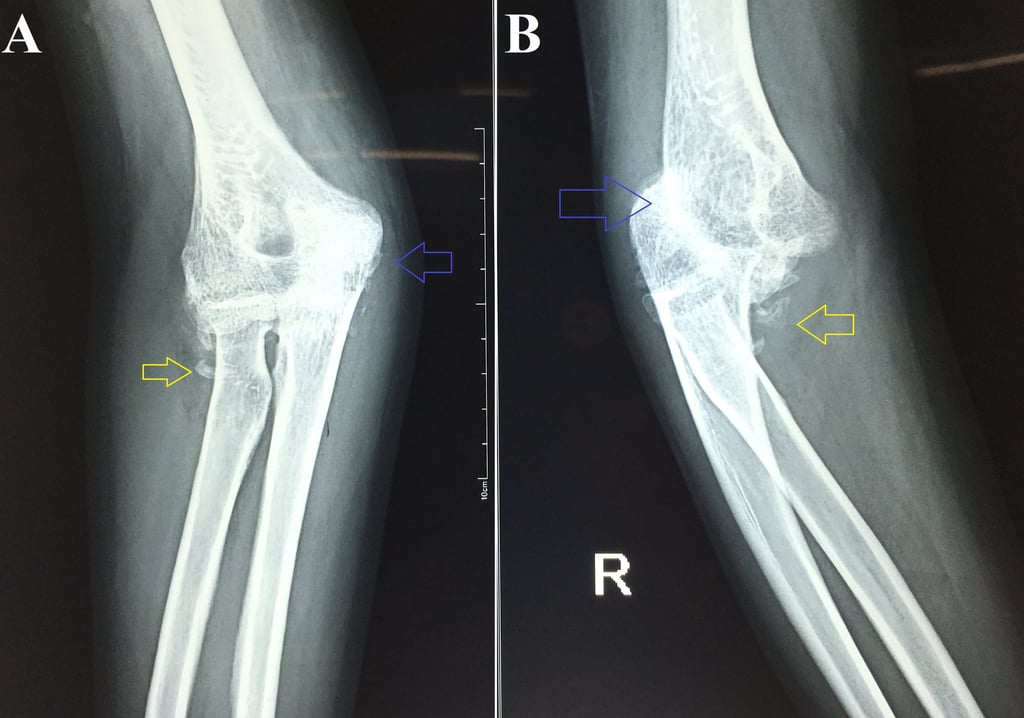

Neglected Elbow Dislocation leading to Ankylosis of Elbow

Neglected elbow dislocation is defined as a dislocation that is present for 3 weeks or longer. This case demonstrates that neglected elbow dislocations can lead to ankylosis of the joint. It also shows how radiographs of the forearm are inadequate to assess for elbow dislocations even if the elbow region is covered in the radiograph.